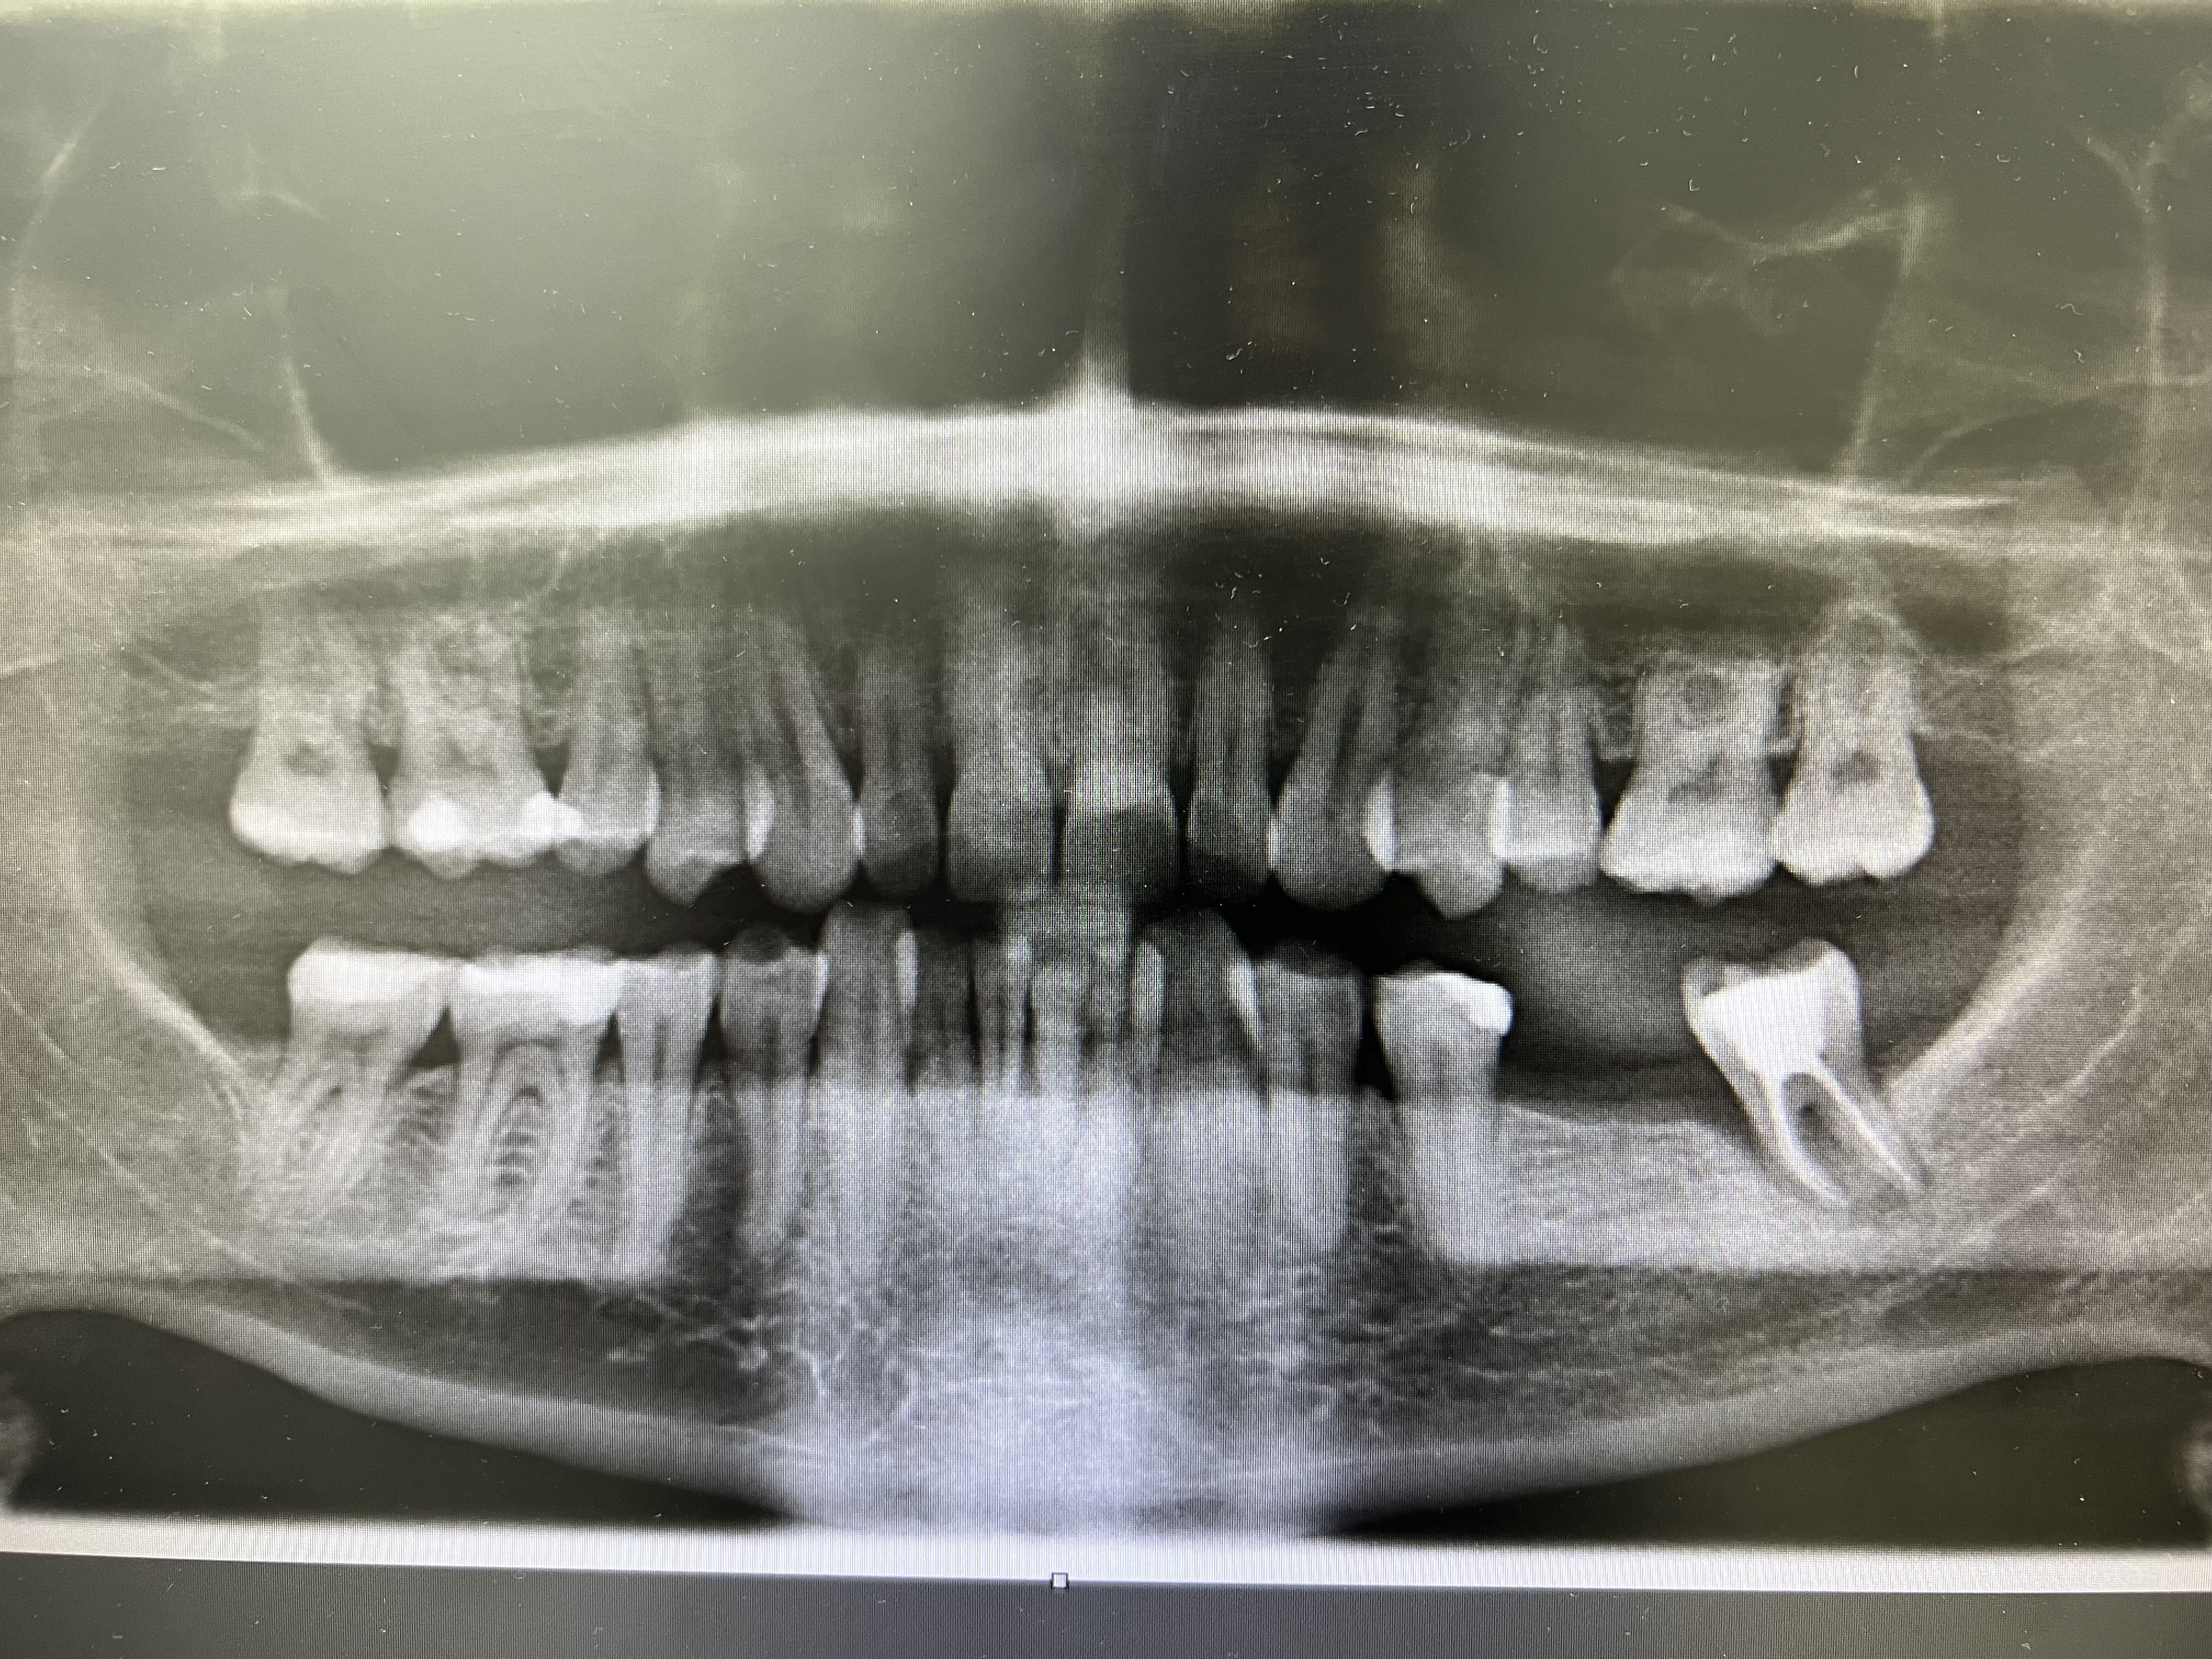

2 Implantate setzen mit Knochenaufbau und Kronen

I. Befund des gesamten Gebisses / Behandlungsplan

Oberkiefer

Unterkiefer

18 17 16 15 14 13 12 11

21 22 23 24 25 26 27 28

48 47 46 45 44 43 42 41

31 32 33 34 35 36 37 38

• Knochenaufbau: 1x Regio 36-37